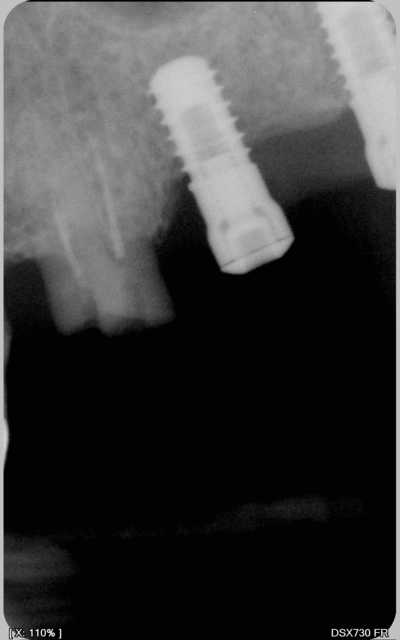

J'ai un patient sur qui des implants ont été posés il y a une dizaine d'année mais la prothèse n'a jamais été réalisée. Son ancien praticien est entre temps parti à la retraite, le cabinet n'a pas été repris, impossible d'avoir des infos de ce coté là.

Donc si quelqu'un reconnait ce type d'implant sur la radio, merci des infos.

Il semble s'agir d'implants cylindriques 1 temps chirurgical et connexion interne (pas de friction?)

possible ONB 8x3,7

Straumann ou un de ses clone ?

Pas l'air très net l'os autour,

Visiblement sans hexagone à cette époque cela me fait penser à la connectique vissée de chez IMZ cylindrique corps vissé. Je crois que c'est Denstply qui a racheté avec Ankylos. Tu peux tjrs leur envoyé un mail pour avis de leur part.

Mais je suis d'accord avec d'autre attention à la mise en charge, l'os ayant commencé à se barrer bien que l'on voit bien radiologiquement le manque d'étanchéité de la vis de couverture.

On dirait un dennar, t'es pas dans la m....

c'est un ONB